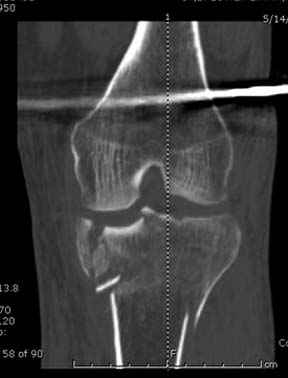

Если там действительная импрессия, пустое место без структуральных заполнителей, кость или синтетические материалы, не восстановится, а образуется коллапс, и ось конечности поведет после нагрузки. Кроме того там возможно "болт стяжка"?, в медиальной стороне выступает за кортекс, можно было укоротить! Потом создается впечатление, что не соответствуют мыщелки большеберцовой и бедренной костей? Покажите снимок.

Ваша упорство с минимальными данными защищаться забавляет, и пока не все убедились в Вашей правоте. Для нормальной защиты необходимы аргументированные доказательства исследованиями. КТ сканы и прицельно сделанные снимки коленного сустава, а так все аргументы - не более чем "моя фиксация, мне нравится". Без этих доказательств пока только Ваше упорство.....